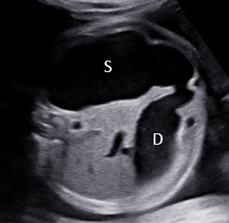

Ca lâm sàng: Fetal fibrosarcoma